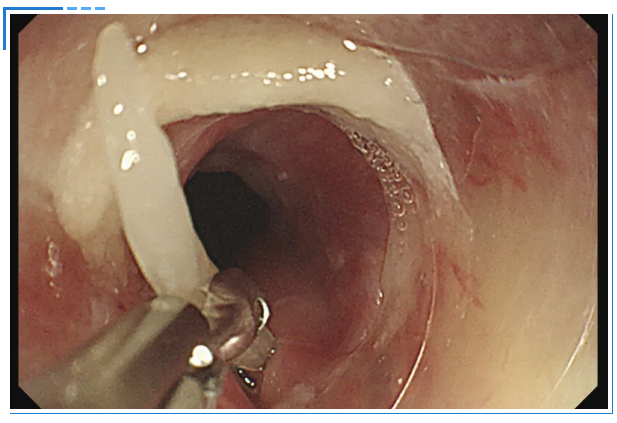

消化内镜室迅速启动取刺准备,当胃镜缓缓抵达食管入口时,清晰可见一根长约3cm的鱼刺,正斜斜嵌顿在食管入口的右侧壁,鱼刺尖端已刺入黏膜下层,周围黏膜因刺激出现明显充血水肿。更棘手的是,鱼刺恰好卡在食管入口的生理拐弯处,这个部位是食管与咽喉的衔接点,角度刁钻,内镜难以稳定固定位置。

操作医生首先尝试使用常规透明帽辅助取刺。透明帽顺利扩张开食管入口,将鱼刺完整暴露在视野中,但当异物钳从内镜操作通道伸出时,问题出现了:由于食管拐弯的角度限制,内镜操作通道与鱼刺的位置夹角过小,异物钳的活动空间被严重压缩。医生反复调整内镜角度和异物钳方向,要么视野被遮挡无法看清鱼刺,要么异物钳无法精准对准鱼刺主体,尝试了数次后,始终无法牢固夹持鱼刺,首次取刺宣告失败。

一切准备就绪后,医生再次为陈女士进行内镜操作。胃镜带着改良后的透明帽缓缓进入食管入口,当鱼刺出现在视野中时,吕主任轻轻旋转胃镜角度,将透明帽的豁口精准对准鱼刺嵌顿的位置。随后缓慢推送胃镜,让鱼刺的一部分稳稳地进入豁口内——此时豁口如同一个“固定卡槽”,将鱼刺牢牢固定住。

紧接着,异物钳从内镜通道中缓缓伸出,借助豁口提供的充足空间,异物钳以最佳角度顺利接近鱼刺,精准地夹住了鱼刺。医生确认夹持牢固后,保持异物钳与胃镜轴线平行,缓慢退镜。退镜过程中,透明帽始终包裹着鱼刺,有效避免了鱼刺尖端划伤食管壁。当胃镜退出口腔时,那根让陈女士痛苦不已的鱼刺被完整取出。